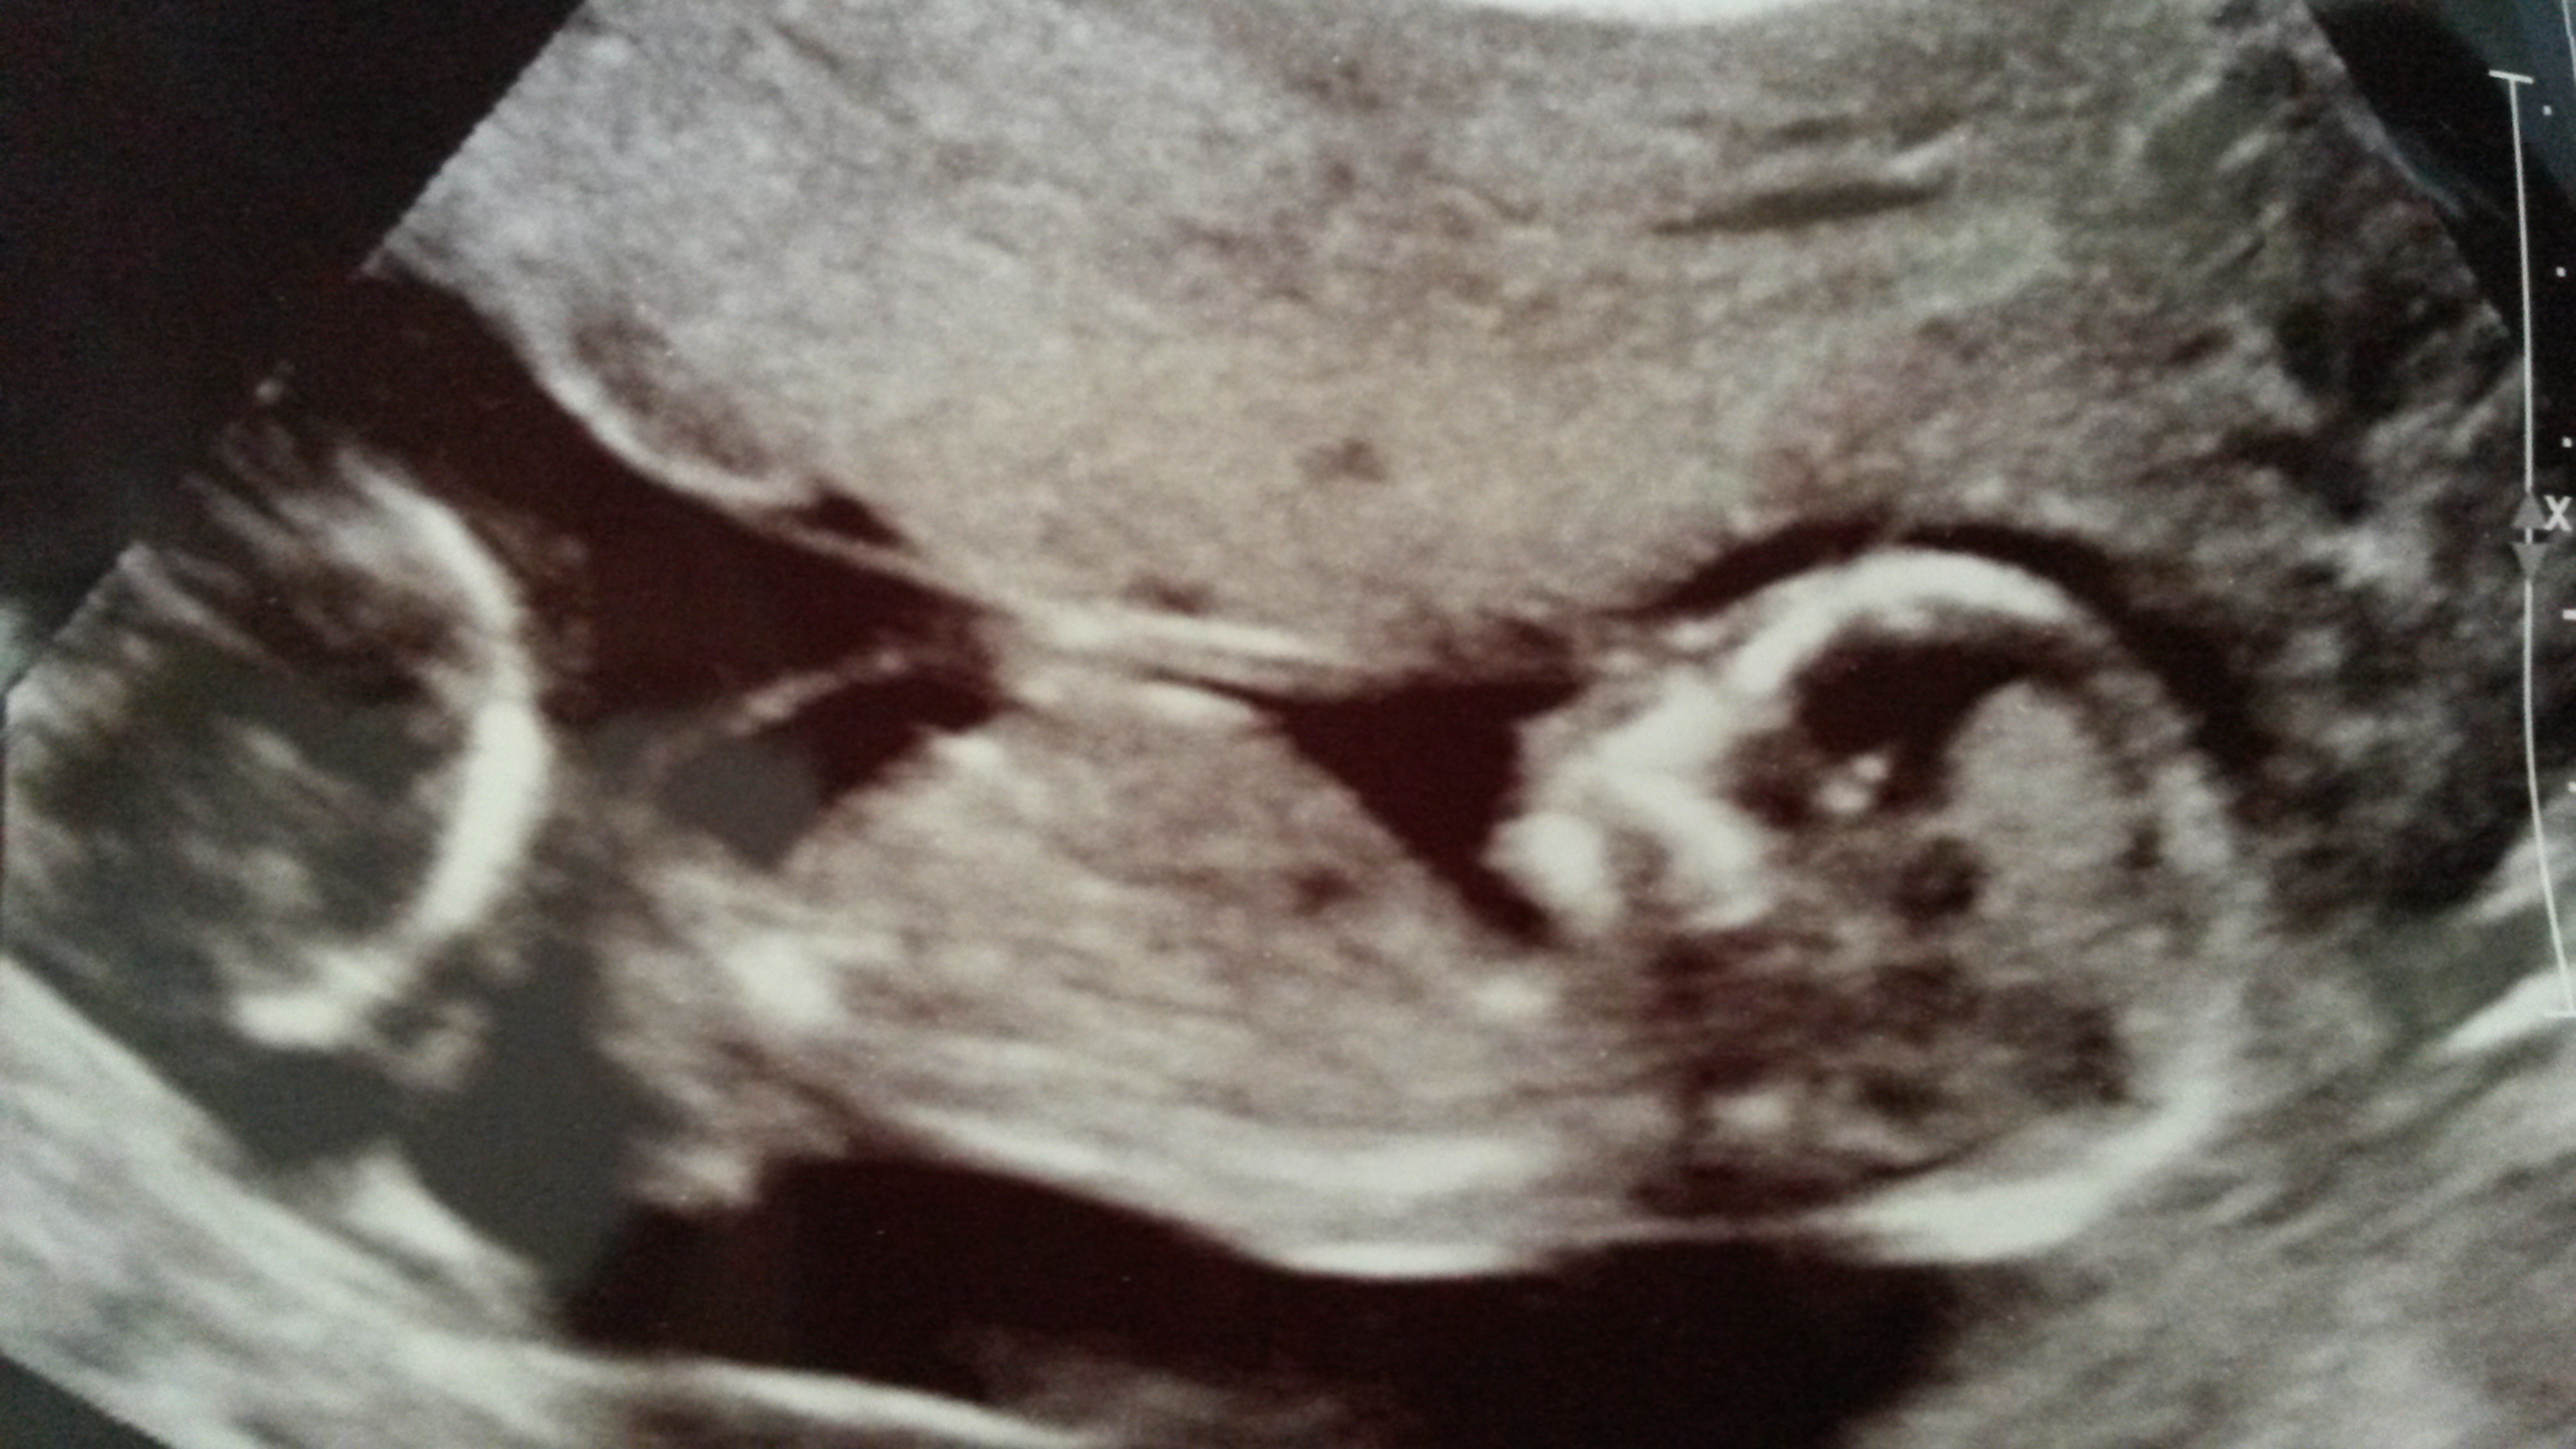

Second pic 12+3